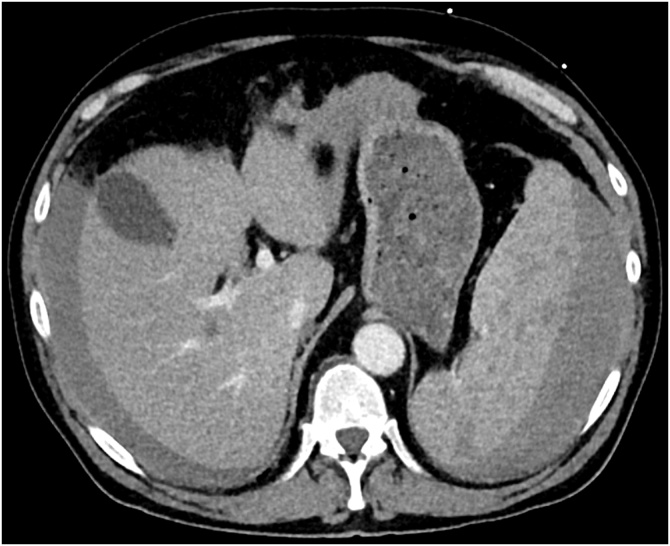

Fig. 3.

Contrast-enhanced axial abdominal computed tomography showing free fluid around the liver and the inhomogeneous splenic parenchyma.

The patient presented afebrile with a blood pressure of 78/43 mmHg and a heart rate of 96/min. On examination we found a ballooned abdomen without signs of peritonitis. The computed tomography showed several hypodense lesions within the spleen and contrast blushes, which were interpreted as splenic rupture with ongoing bleeding (Fig. 3). Emergent diagnostic angiography revealed no active bleeding but a large subcapsular splenic hematoma. A selective embolization was not possible and therefore a proximal splenic artery embolization was performed. Five days after the embolization an open splenectomy was performed showing three liters of clotted blood within the abdominal cavity.